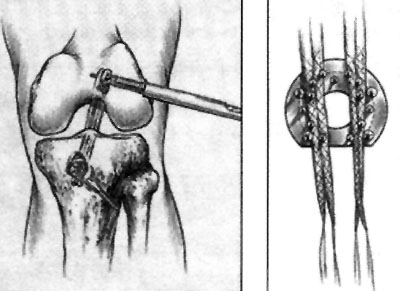

08_02_02_fig1

Luego de la medición de ambos injertos se procede a la ubicación de la guía one step la cual ingresa por el mismo abordaje utilizado para la toma de injertos. Se labra el túnel tibial en extensión a fin de evitar rozamientos permitiendo con esto reducir al mínimo la notchplastia.

08_02_02_fig2

Luego de la liberación del remanente del LCA se labra túnel femoral y se coloca la guía de ingreso lateral para el tornillo Bone Mulch, la misma se utiliza a su vez para medir la longitud del tornillo.

08_02_02_fig3

Colocado el ligamento y luego de la fijación distal con una arandela multipunto y su respectivo tornillo, se coloca injerto óseo obtenido luego de la remoción de una camisa que se le coloca previamente a las mechas utilizadas para los túneles y destinada a tal fin. Al final del procedimiento se agrega una contratuerca al tornillo Bone Mulch que tiene como función evitar la migración del injerto óseo colocado y sirve a su vez para una futura revisión de la técnica.